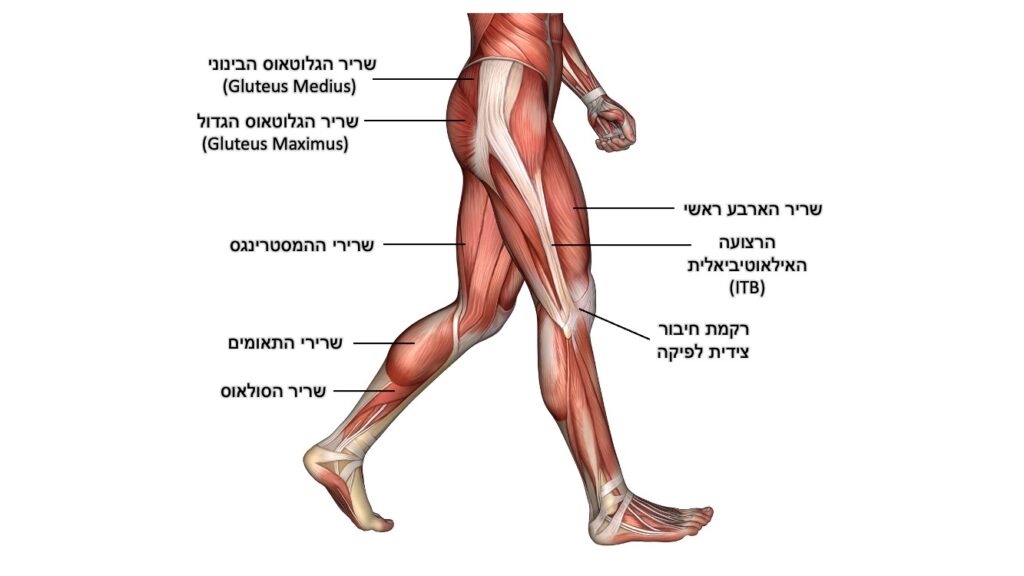

- חולשת שרירים – חולשה יחסית של שרירים בפלג הגוף התחתון, בדגש על השרירים סביב מפרק הירך והשריר הארבע-ראשי. חולשה שרירית תוביל, בין השאר, לשליטה מופחתת על הפיקה במהלך התנועה שלה על פני הטרוכלאה ולעומסים מוגברים במדור.

- נוקשות רקמות וחוסר גמישות – בדגש על: שרירי ההמסטרינגס (מכופפי הירך), הארבע ראשי (מיישר הברך), התאומים והסולאוס (מכופפים כפיים של הקרסול/כף רגל), הרצועה האילאוטיבילית (ITB) ורקמת החיבור הצידית לפיקה.

- חיזוק ותרגול של שרירים סביב הירכיים והברכיים – בדגש על שרירי הארבע ראשי (QUADRICEPS), מרחיקי הירך (GLUTEUS MEDIUS) ופושטי הירך (GLUTEUS MAXIMUS). הכאב אומנם מורגש בברך, אך גם לתפקוד ולחוזק של השרירים סביב הירך יש תפקיד מפתח בשיפור הכאבים.